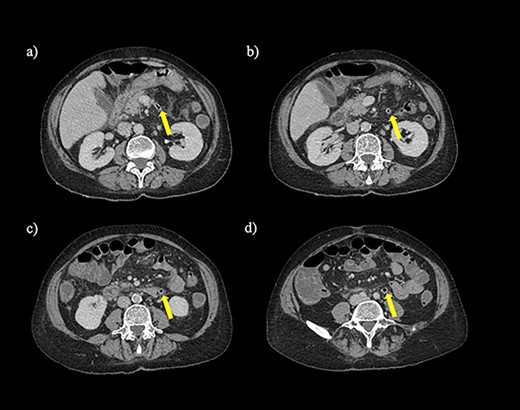

A non-contrast-enhanced computed tomography (CT) scan of the abdomen and pelvis was performed. This demonstrated acute sigmoid diverticulitis with air tracking along the course of the inferior mesenteric vein (Figs 1 and 2). Additionally, a large portal vein thrombus was seen with extension to the left intrahepatic portal vein (Fig. 3) and evidence of portal venousgas.

Axial section of a non-contrast CT scan with showing air tracking within the inferior mesenteric vein at various levels (yellow arrow).